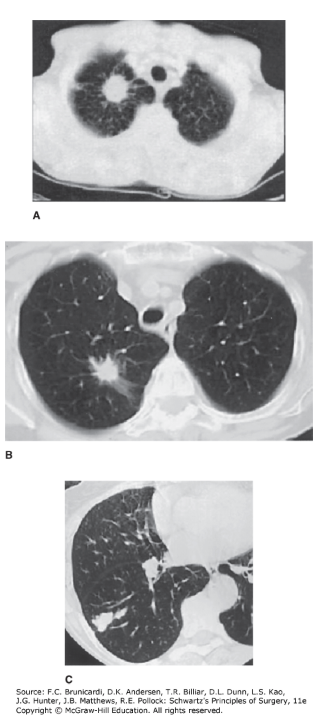

Computed tomography scan images of solitary pulmonary nodules. A. The corona radiata sign demonstrated by a solitary nodule. Multiple fine striations extend perpendicularly from the surface of the nodule like the spokes of a wheel. B. A biopsy-proven adenocarcinoma demonstrating spiculation. C. A lesion with a scalloped border, an indeterminate finding suggesting an intermediate probability for malignancy.

In general, malignant neoplasms are larger and grow rapidly, appear spiculated, often with surface umbilication or notching and eccentric excavation. In addition, cancers often occur in smokers (or former smokers) over the age of 40 with negative skin tests for tuberculosis, histoplasmosis, or coccidioidomycosis (although positive tests do not exclude cancer), and in nodules that lack calcium (CT Hounsfield units < 175). In contrast, benign lesions are small (< 1 cm), stable (> 2 years), and calcified ("target" or "popcorn" distribution; CT Hounsfield units > 175) and are associated with positive skin tests in 70–90% of patients. Evaluation of these patients usually includes chest CT scan, but sputum cytology, cultures, bronchoscopy, and mediastinoscopy are sometimes helpful. FDG-PET scanning plays an important role in the evaluation of tumors that are suspicious for malignancy. PET scan can often differentiate among lesions suspicious for malignancy.